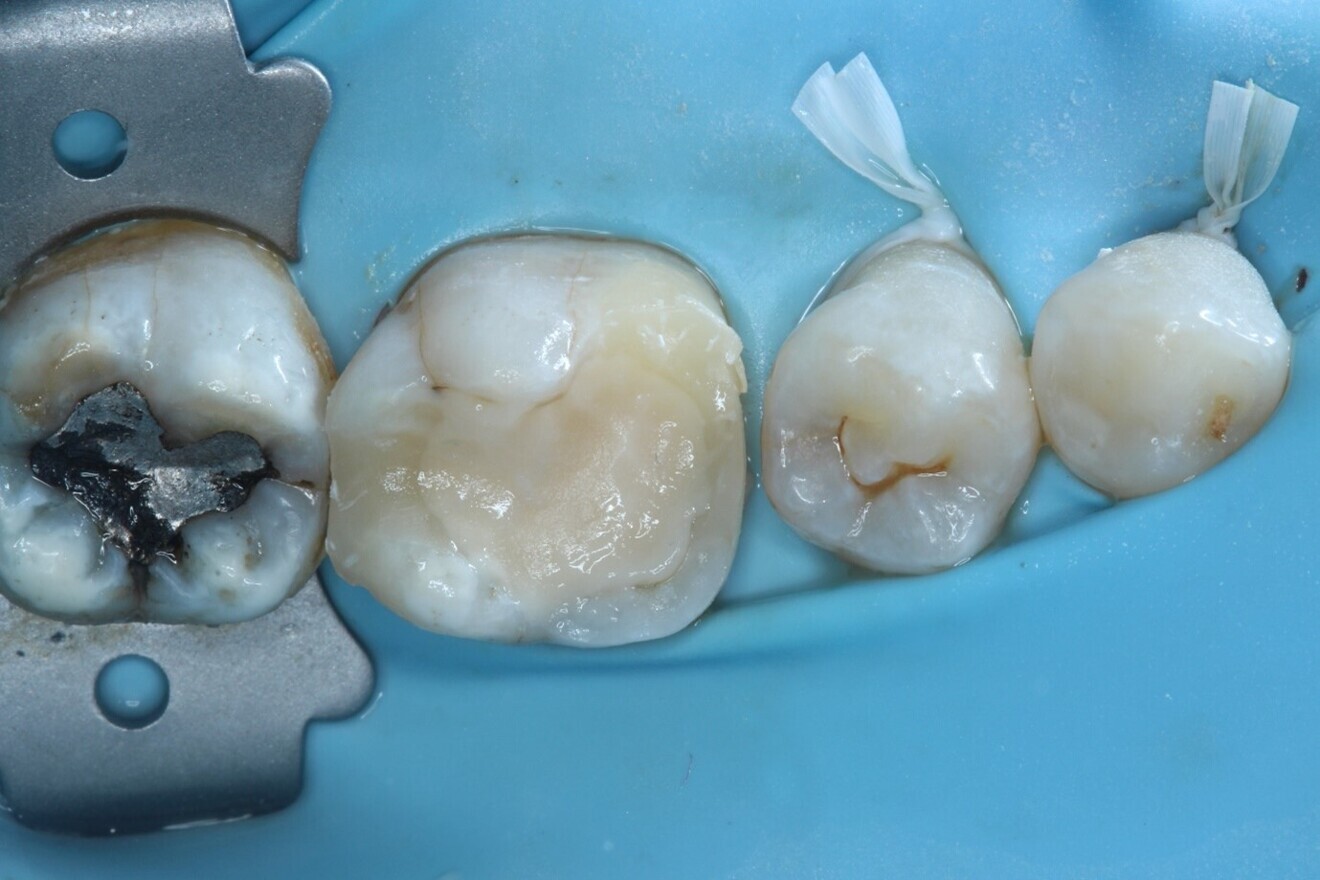

The canals were dried with paper points, a calcium hydroxide paste was placed in the canals and PTFE tape was used in the pulp chamber space. In order to improve the fracture resistance of the tooth in between appointments, deep marginal elevation was carried out with composite for the mesial marginal ridge, utilising a band-in-band technique. The tooth was temporarily restored with a glass ionomer cement, and the occlusion and contacts checked (Figs. 6–8).

Fig. 8: Interim glass ionomer cement restoration placed to allow re-establishing of access to the canals at the next visit.